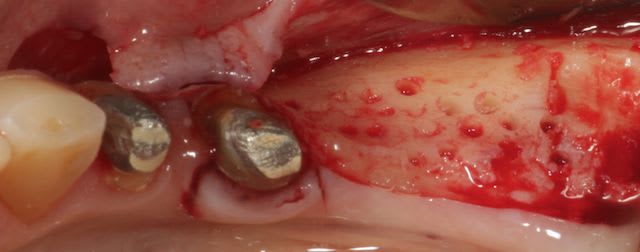

Cas 1-coté gauche maintenant:

1- ouverture, forme et configuration différente

2- une fois échauffée avec le coté droit, je me dis allez hop, j'attaque une expansion. donc incision crestale avec décharges osseuses

3- mise en place des expanseurs de Mesinger A et B

4-5 notez que l'incision de décharge étant oblique , elle sert également de garde fou contre une éventuelle fracture osseuse. l'os "mobile" vient buter contre l'os "immobile"

la suite en primeur pour ceux qui viennent à Sallanches les 28 et 29 Mars...